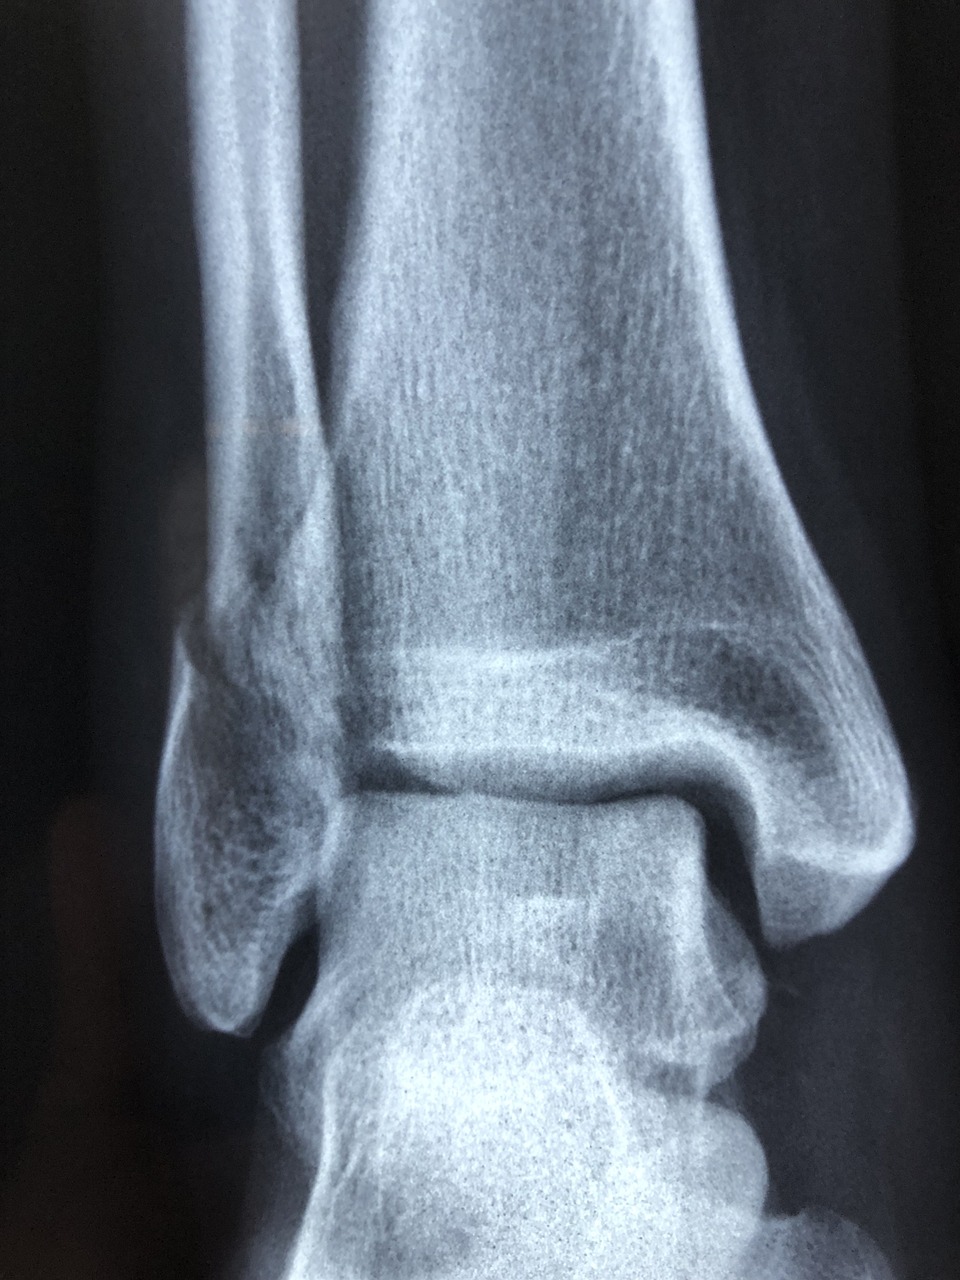

골다공증은 뼈의 밀도가 줄어들고 구조가 약해져 쉽게 부러지는 질환입니다.

세계보건기구(WHO)는 골다공증을 “전 세계적으로 노인성 질환 중 가장 빠르게 증가하는 질환”으로 분류하고 있으며,

골절로 인한 사망률과 합병증 위험은 암, 심혈관질환 다음으로 높게 보고됩니다.